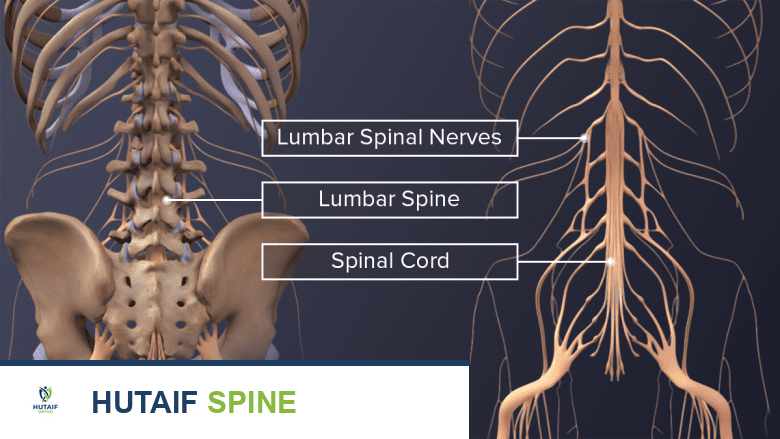

التشريح الدقيق للعمود الفقري القطني: فهم الأساسيات

لفهم كيف تعمل جراحات ALIF واستئصال الجسم الفقري، يجب أولاً أن نفهم التشريح المعقد للعمود الفقري القطني (أسفل الظهر). يتكون العمود الفقري القطني من خمس فقرات كبيرة وقوية يُشار إليها بالرموز من L1 إلى L5. هذه الفقرات تحمل الجزء الأكبر من وزن الجسم وتوفر المرونة اللازمة للحركة والانحناء.

مكونات القطعة الفقرية (Spinal Segment)

تتكون كل قطعة فقرية من:

1. الجسم الفقري (Vertebral Body): الكتلة العظمية الأسطوانية الكبيرة في الجزء الأمامي من الفقرة، وهي التي تتحمل الضغط.

2. القرص بين الفقرات (Intervertebral Disc): يعمل كوسادة لامتصاص الصدمات بين الأجسام الفقرية. يتكون من:

* الحلقة الليفية (Annulus Fibrosus): الغلاف الخارجي القوي والمرن.

* النواة اللبية (Nucleus Pulposus): المركز الهلامي الناعم الذي يوفر خاصية امتصاص الصدمات.

3. القناة الشوكية (Spinal Canal): الممر الذي يمر من خلاله الحبل الشوكي وجذور الأعصاب (ذنب الفرس في المنطقة القطنية).

4. المفاصل الوجيهية (Facet Joints): مفاصل صغيرة في الجزء الخلفي من العمود الفقري توجه وتحد من حركة الفقرات.

عندما يحدث خلل في أي من هذه المكونات، سواء بسبب التقدم في العمر، أو الإصابات، أو الأمراض، يختل التوازن الميكانيكي الحيوي بأكمله، مما يؤدي إلى الألم والضغط العصبي.